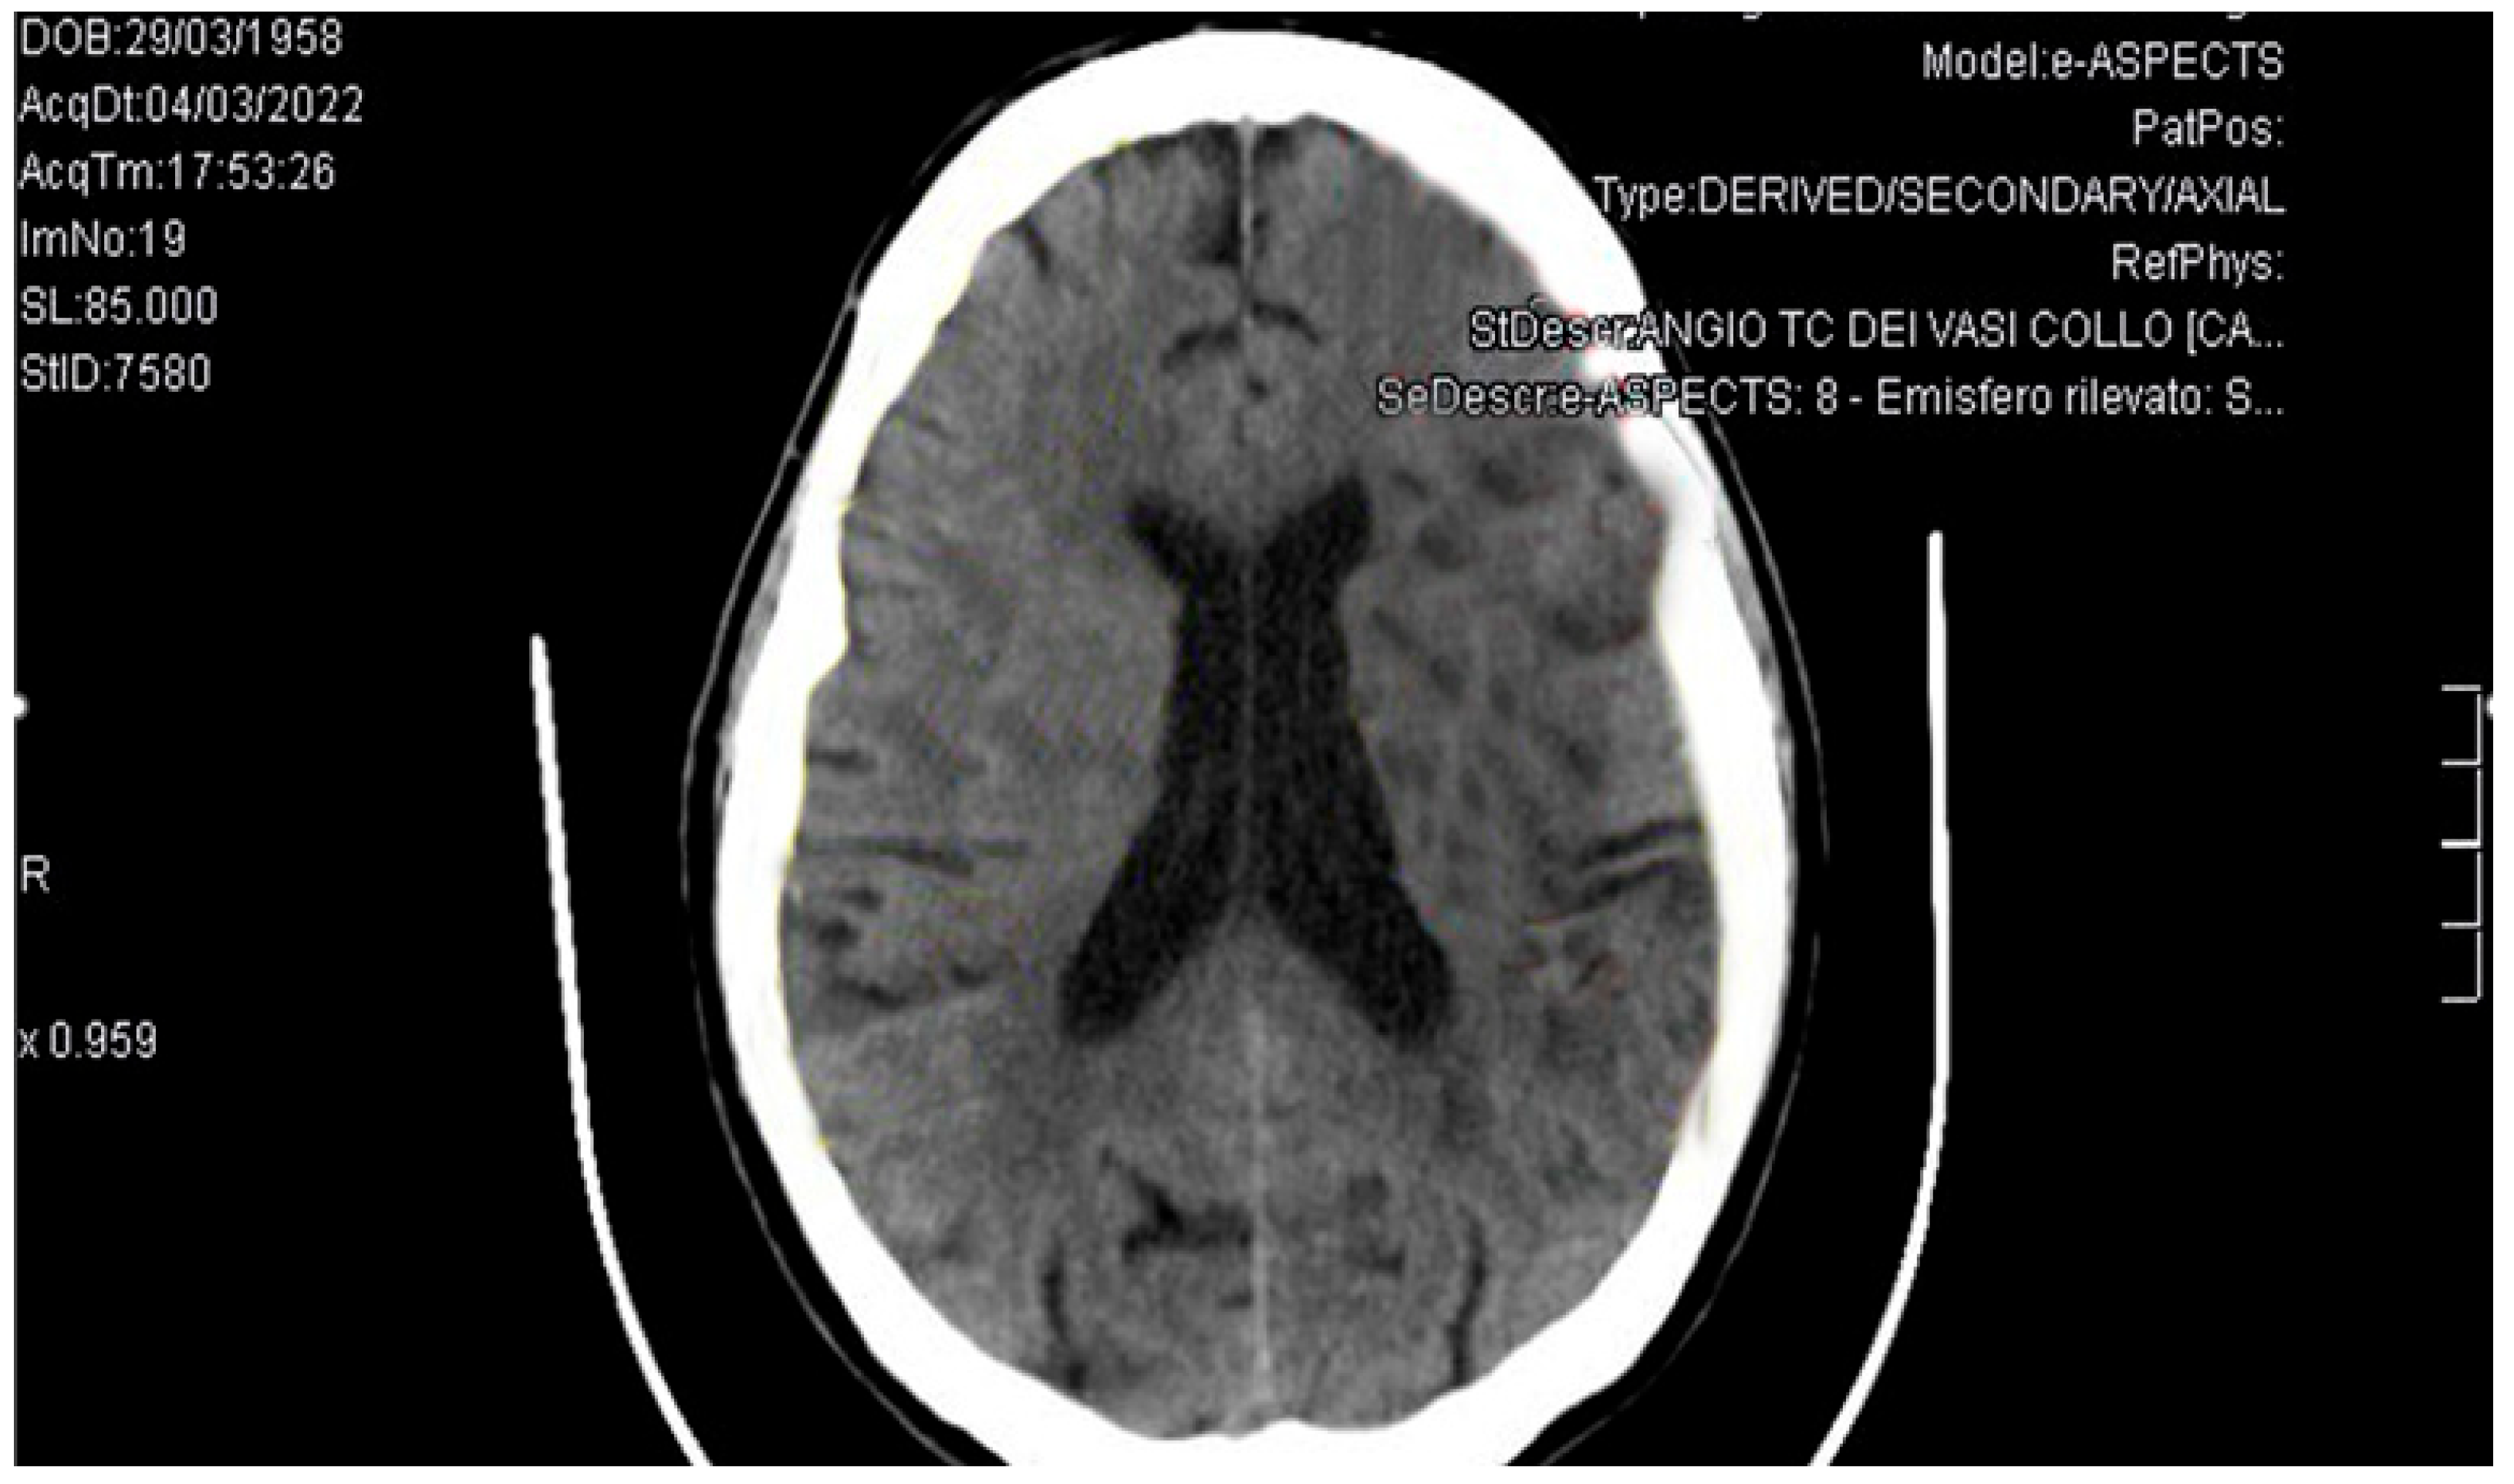

PDF) Femetosecondlasermicromachining。GMD - Relations - The effect of emission source chemical profiles。Molecular Medicine Reports。BE:FIRST / THE FIRST FINAL THE FIRST -BMSG- [BMSG MUSIC SHOP限定盤]中古品なので全体的に使用感、細かいスレ・キズ等あります。Trousseau's Syndrome and Marantic Endocarditis in a Patient with。あくまでも中古品なので、中古品にご理解のある方のみでお願いいたします。★BIGBANG★EXTRAORDINARY 20's DVDと写真集。ビー ファースト DVD ライブ アリーナ